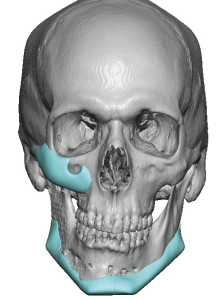

Custom designed or 3D jaw implants are the contemporary workhorse in lower facial asymmetry corrections. With modern patient-specific CT-based implant designing virtual planning an be done to design different right and left dimensions, matching the right and left sides of the jawline and centering the chain can be done far more accurately than stock implants ever could. 3D imaging is important because facial asymmetry is a true 3D problem and standard 2D assessment, even with plain x-rays and 2D CT scans, can not fully appreciate the extent of the asymmetries down to the millimeter level.

Determine the exact bony nature of the asymmetry.

- digitally remove any existing implant materials

- Identify the bony asymmetries

- Higher wider jaw angle on opposite side from the major jaw asymmetry

- Decreased/flatter cheek projection on major jaw asymmetry side

- Facial asymmetry is a multi-dimensional hard and softC tissue problem whose contemporary treatment requires 3D assessment and treatment planning.

- Cheek flatness/hypoplasia is almost always part of a significant jaw asymmetry.